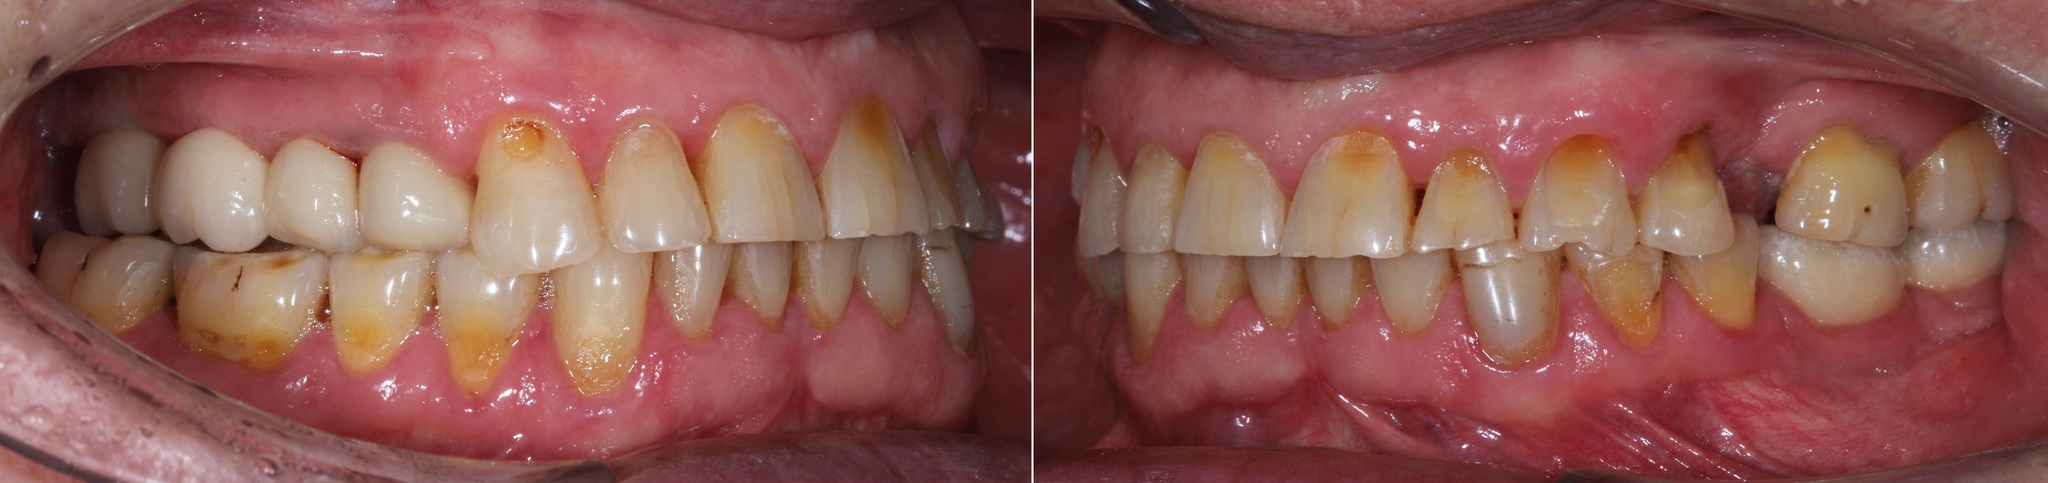

Обратите внимание, как сильно истерты зубы, а в области шеек этих зубов – клиновидные дефекты (некариозное поражение твердых тканей зубов, при которых зуб приобретает форму клина).

Основной причиной появления клиновидных дефектов является перегрузка из-за неправильного смыкания зубов.

Зубы за 3.5 года жизнь потрепала. Режущие края истерлись, появилось больше клиновидных дефектов:

Особенно не выдержал натиска времени 6й верхний левый зуб: